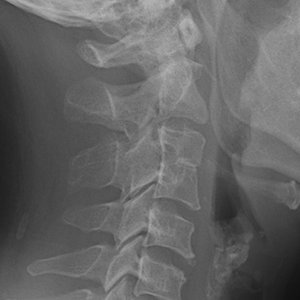

Congenital fusion of cervical vertebrae is a rare anomaly, occurring when two or more cervical vertebrae are congenitally fused. (Fig. 1) This anomaly goes by several names: cervical vertebral fusion syndrome (CVFS), Klippel-Feil syndrome (KFS), congenital dystrophia brevicollis, and Klippel-Feil deformity.1 I consider congenital fusion of cervical vertebrae (CFCV) a better descriptive term, but the literature and most of the research articles refer to Klippel-Feil Syndrome, so to avoid confusion, I will, too.

With KFS, there is fusion of two vertebrae which appear structurally as one and function essentially as one motor unit.2 It is rare to have more than two adjacent segments fused together.3 KFS can be distinguished from acquired fused cervical vertebrae such as fusion due to TB, RA or even surgery by two factors: 1) a decrease in the sagittal diameter of the vertebrae, particularly at the site of fusion; and 2) total height of the fused vertebrae is equal to the fused vertebrae's height, including the intervertebral disc.

Additional observations are that the intervertebral discs are absent or there is margin of sclerosis where the "normal" endplates of the segments would have developed. The transverse foramina are smooth; there is a single spinous process for the two vertebral bodies. (Fig. 1)

Congenital fusion - Copyright – Stock Photo / Register Mark FIG 1 Congenital fusion of C3 and C4. This anomaly may or may not be symptomatic.4 Often in children there are no symptoms, but with age, even in young adulthood, myelopathy, limitation in neck movement, muscular atrophy and regional sensory loss may develop associated with this anomaly.